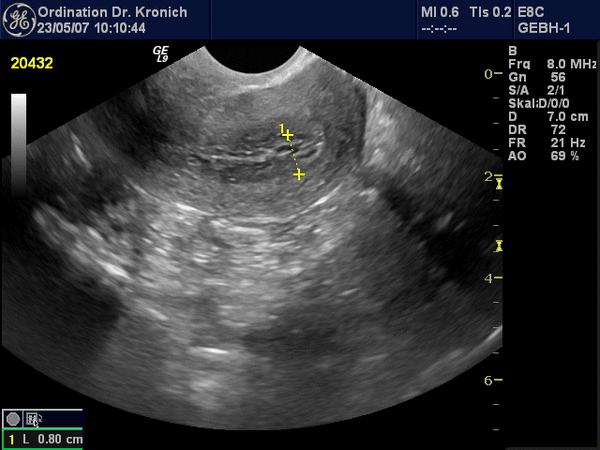

Линейный эндометрий – термин, который часто встречается в заключениях ультразвуковых исследований. Что же он обозначает? Эндометрий состоит из трех слоев: базального (который не обновляется), функционального (обновляющегося ежемесячно) и эпителиального (покровного). В первой и частично во второй фазах менструального цикла все эти слои обладают схожими показателями проницаемости, плотности и эхогенности. При этом границы между слоями имеют значительно более высокую эхогенность, что позволяет визуализировать их на исследовании в виде четких прямых линий, что и дало повод для использования данного термина.

Таким образом, наличие линейного эндометрия на первой и частично на второй фазе цикла считается нормальным и является важным условием для успешного зачатия. Однако, если подобное состояние наблюдается на других этапах цикла, это может указывать на наличие патологии.